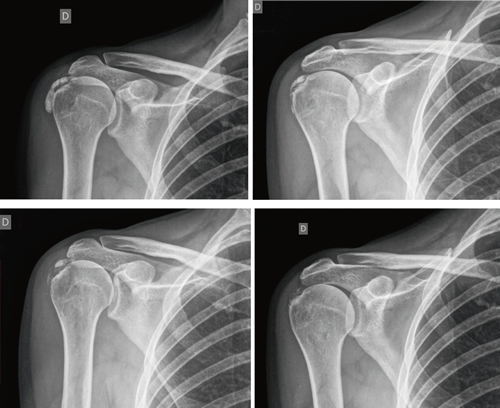

The average number of sessions in our series was 20. The criteria for continuing or stopping treatment was the radiological and clinical evolution (Figures 4 and 5). The interventions were performed up to a maximum of 40 sessions. Perrón treated patients for 9 sessions (3 weekly sessions for 3 weeks) (14). Leduc treated with 10 sessions (3 per week for the first two weeks; then one weekly for 4 weeks) (15). Rioja-Toro treated patients for 40 sessions (5 times per week) and evaluated them at 20 and 40 sessions (3). Chico-Álvarez treated patients between 15 and 30 sessions depending on the radiological evolution (5 times per week) (1).

Fig. 5. A 44-year-old female patient, with calcific tendinitis of the left supraspinatus, of the resorptive type, who after 20 sessions of iontophoresis decreased pain measured by VAS from 10/10 to 4/10, and calcification from 22 mm to 0 mm (complete disappearance).